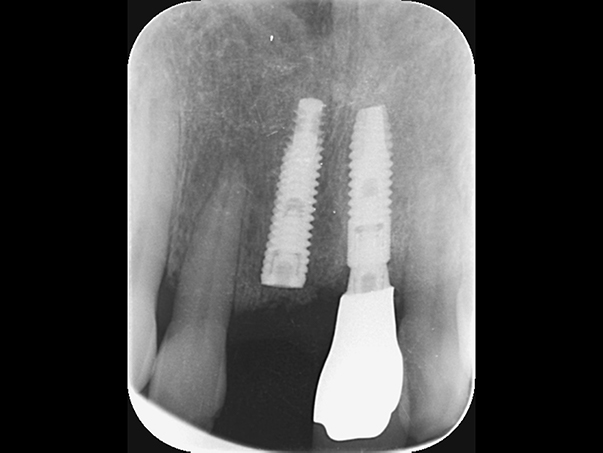

インプラントが2本入っているが左右でインプラント体の種類が異なります。

麻布十番歯科の左右で異なるインプラント体を使用したレントゲン写真

上顎では上顎洞にインプラントを入れないようにするために、ソケットリフトという骨を足す手術を行うことがあります。 当院ではこちらの手術はインプラント手術とは別に約15万円かかります。

麻布十番歯科のソケットリフト手術後のレントゲン写真